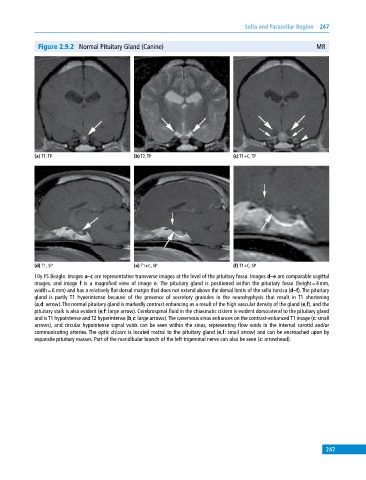

Figure 2.9.2 Normal Pituitary Gland (Canine) MR

(a) T1, TP (b) T2, TP (c) T1+C, TP

(d) T1, SP (e) T1+C, SP (f) T1+C, SP

10y FS Beagle. Images a–c are representative transverse images at the level of the pituitary fossa. Images d–e are comparable sagittal

images, and image f is a magnified view of image e. The pituitary gland is positioned within the pituitary fossa (height = 4 mm,

width = 6 mm) and has a relatively flat dorsal margin that does not extend above the dorsal limits of the sella turcica (d–f). The pituitary

gland is partly T1 hyperintense because of the presence of secretory granules in the neurohyphysis that result in T1 shortening

(a,d: arrow). The normal pituitary gland is markedly contrast enhancing as a result of the high vascular density of the gland (e,f), and the

pituitary stalk is also evident (e,f: large arrow). Cerebrospinal fluid in the chiasmatic cistern is evident dorsolateral to the pituitary gland

and is T1 hypointense and T2 hyperintense (b,c: large arrows). The cavernous sinus enhances on the contrast‐enhanced T1 image (c: small

arrows), and circular hypointense signal voids can be seen within the sinus, representing flow voids in the internal carotid and/or

communicating arteries. The optic chiasm is located rostral to the pituitary gland (e,f: small arrow) and can be encroached upon by

expansile pituitary masses. Part of the mandibular branch of the left trigeminal nerve can also be seen (c: arrowhead).